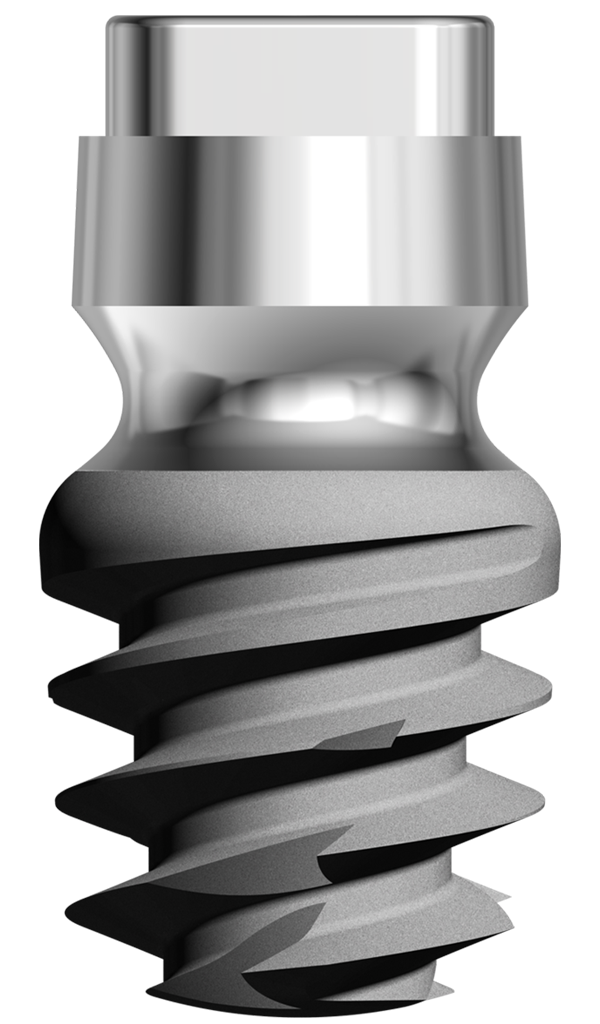

L’implant twinKon® est un implant type Tissue Level.

Sur le plan parodontal, la gestion du profil d’émergence a été revisitée de façon à favoriser le réaménagement d’un joint muqueux épais de première intention qui a vocation à jouer le rôle de barrière naturelle.

Le positionnement vertical de l’implant est légèrement modulable selon le biotype parodontal. L’interface prothétique est décalée au dessus du joint muqueux ; le risque de contamination iatrogène lors des phases de restauration prothétique est réduit.